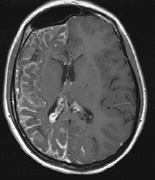

Intracranial leptomeningeal capillary vascular malformation (Figs. 21 and 22) is associated with seizures and contralateral neuromuscular weakness. Central nervous system involvement correlates highly with ipsilateral involvement of the V1 dermatome by a PWS.208,218

Fig. 22. Axial T2-weighted (a) and coronal T1-weighted (b) images of a 16-year-old boy with a port-wine lesion over the right side of his face. The right hemisphere is markedly atrophic and abnormal draining veins are seen within the right lateral ventricle (arrowheads). (c, d) The entire right hemisphere is covered by an enhancing pial angioma and the choroid plexi are enlarged. Enhancing retinal angiomas (arrows), typical of Sturge-Weber syndrome, are seen in (d).